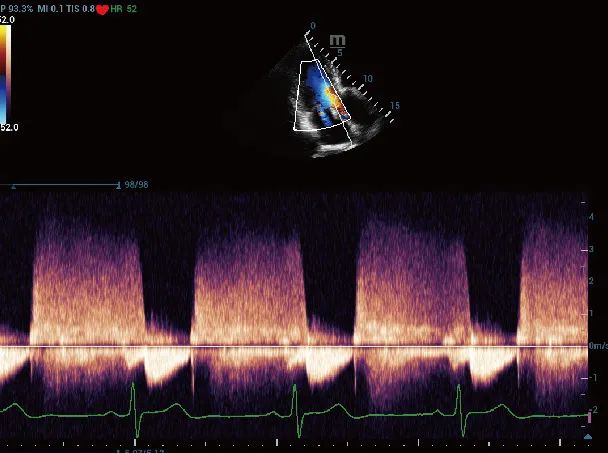

强大的心脏彩超多普勒

依靠高性能彩色多普勒超声功能,作用于心脏大血管系统,可发现相应心脏当中的缺损部位及心脏瓣膜的扩张、狭窄、病变,以及相应大血管的动脉粥样硬化,还有相应血栓等情况,具有多角度、多方位观察功能,且显像清晰,诊断准确率高。

主动脉反流